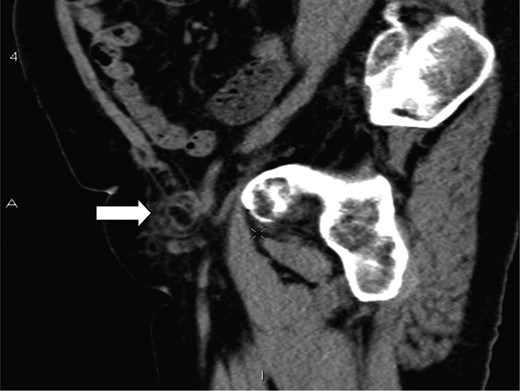

A 70-year-old female was referred by her general practitioner to our radiology department after presenting with a painless right groin swelling. An ultrasound scan showed a lymph node in the right groin with surrounding fluid and unusual appearances not typical of a hernia. A limited CT scan was subsequently performed which revealed a right femoral hernia containing the tip of the vermiform appendix with surrounding inflammatory change and an associated enlarged lymph node in keeping with a De Garengeot's hernia (Figs 1–3). On questioning, the patient first noticed the lump 2 weeks prior to presentation and said that it has gradually increased in size. It was not painful and she had no obstructive symptoms. Her medical history included COPD, breast cancer and a past history of tuberculosis.

A saggital section demonstrating the tip of the appendix (white arrow) within the femoral sac.